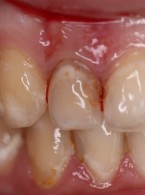

Pokrycie mnogich recesji dziąsłowych

metodą płata przesuniętego dokoronowo z wykorzystaniem przeszczepu podnabłonkowej tkanki łącznej i kolagenowego materiału ksenogennego po wcześniejszej rekonstrukcji połączenia szkliwno-cementowego - opis przypadku